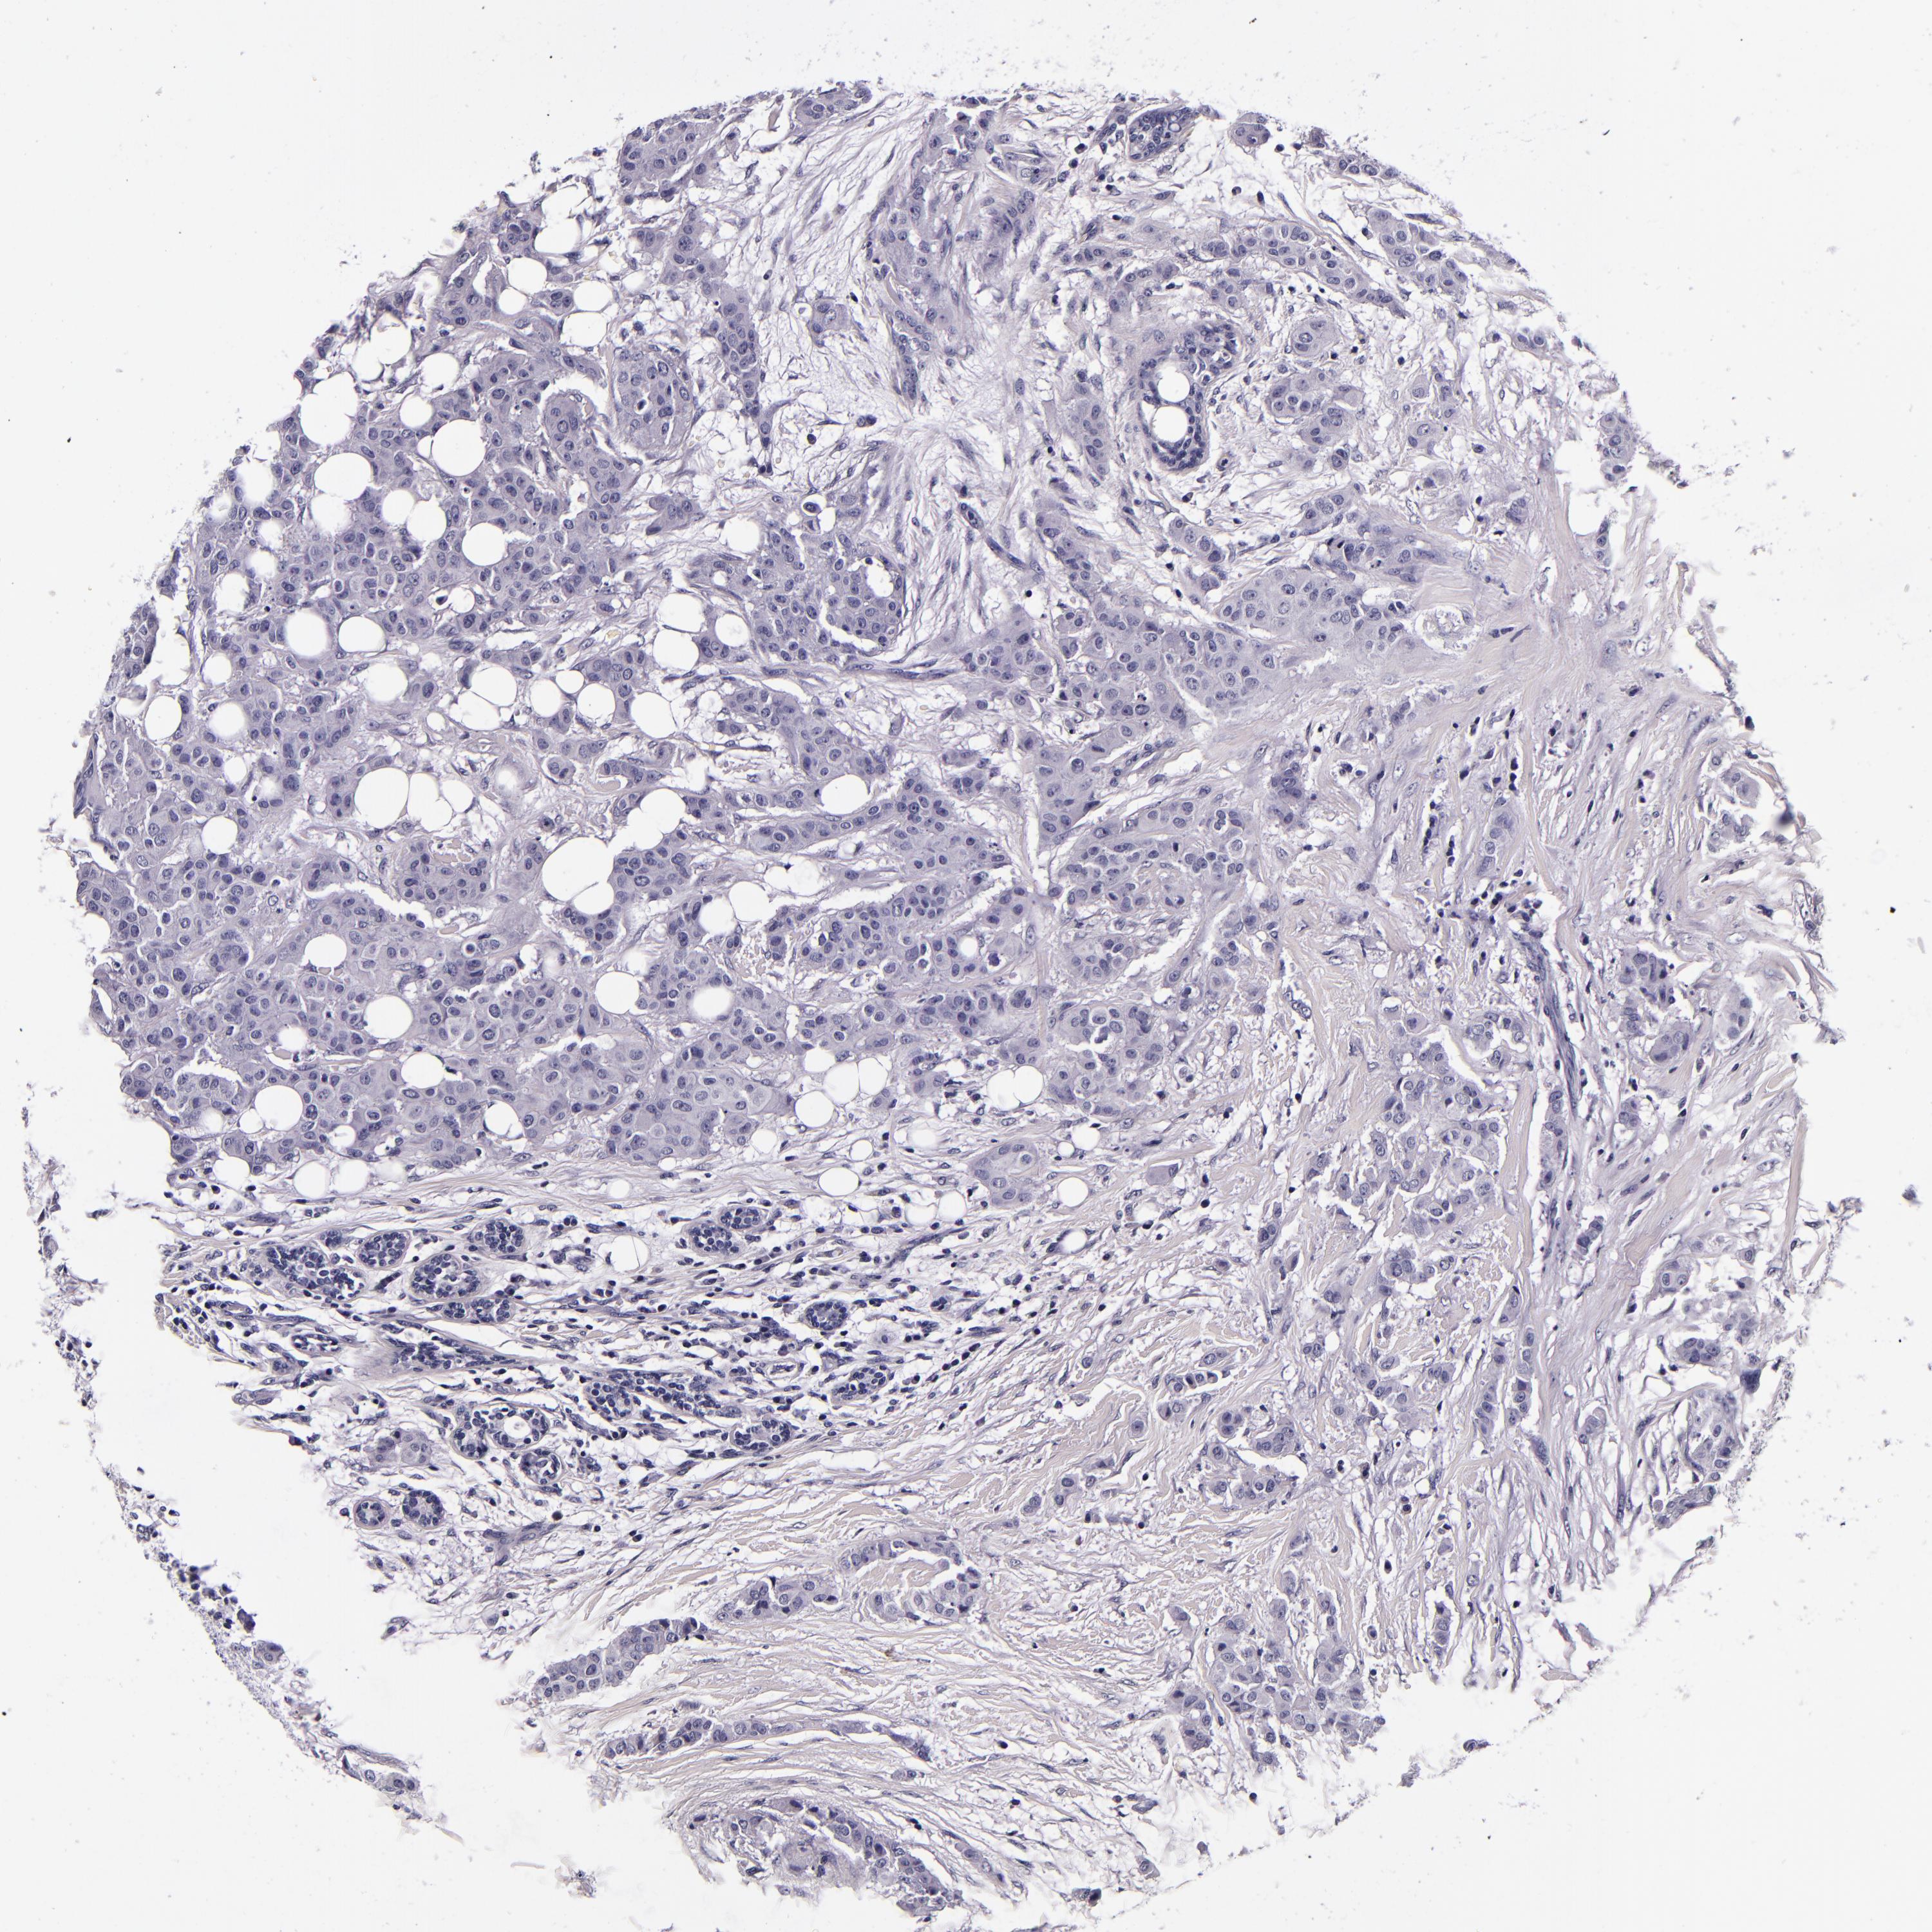

BRCA TCGA BRCA VALIDATION PROTEIN EXPRESSION

Breast cancer

Human cancer